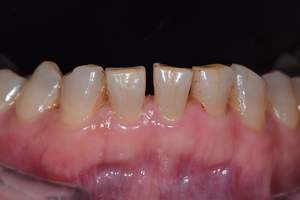

歯石除去

治療前

治療後

| 年齢 | 40歳・男性 |

|---|---|

| 主訴 | 歯石をとりたい |

| 治療内容 | 歯石除去 |

| 治療期間 | 30分 |

| 費用 | 約2,000円 |

| リスク・副作用 | ・歯ぐきの炎症が強いと歯石を取る際に出血することがあります。 ・処置後に歯がしみることがあります。 ・歯と歯の間に隙間ができるので、息が漏れ発音しにくいと感じることがあります。 ・歯ぐきの炎症が軽減すると歯ぐきが引き締まり、歯が長く見えることがあります。 |